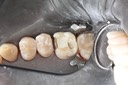

Larry Fujioka #12-12 caries removal

Larry Fujioka #11-12 caries removal